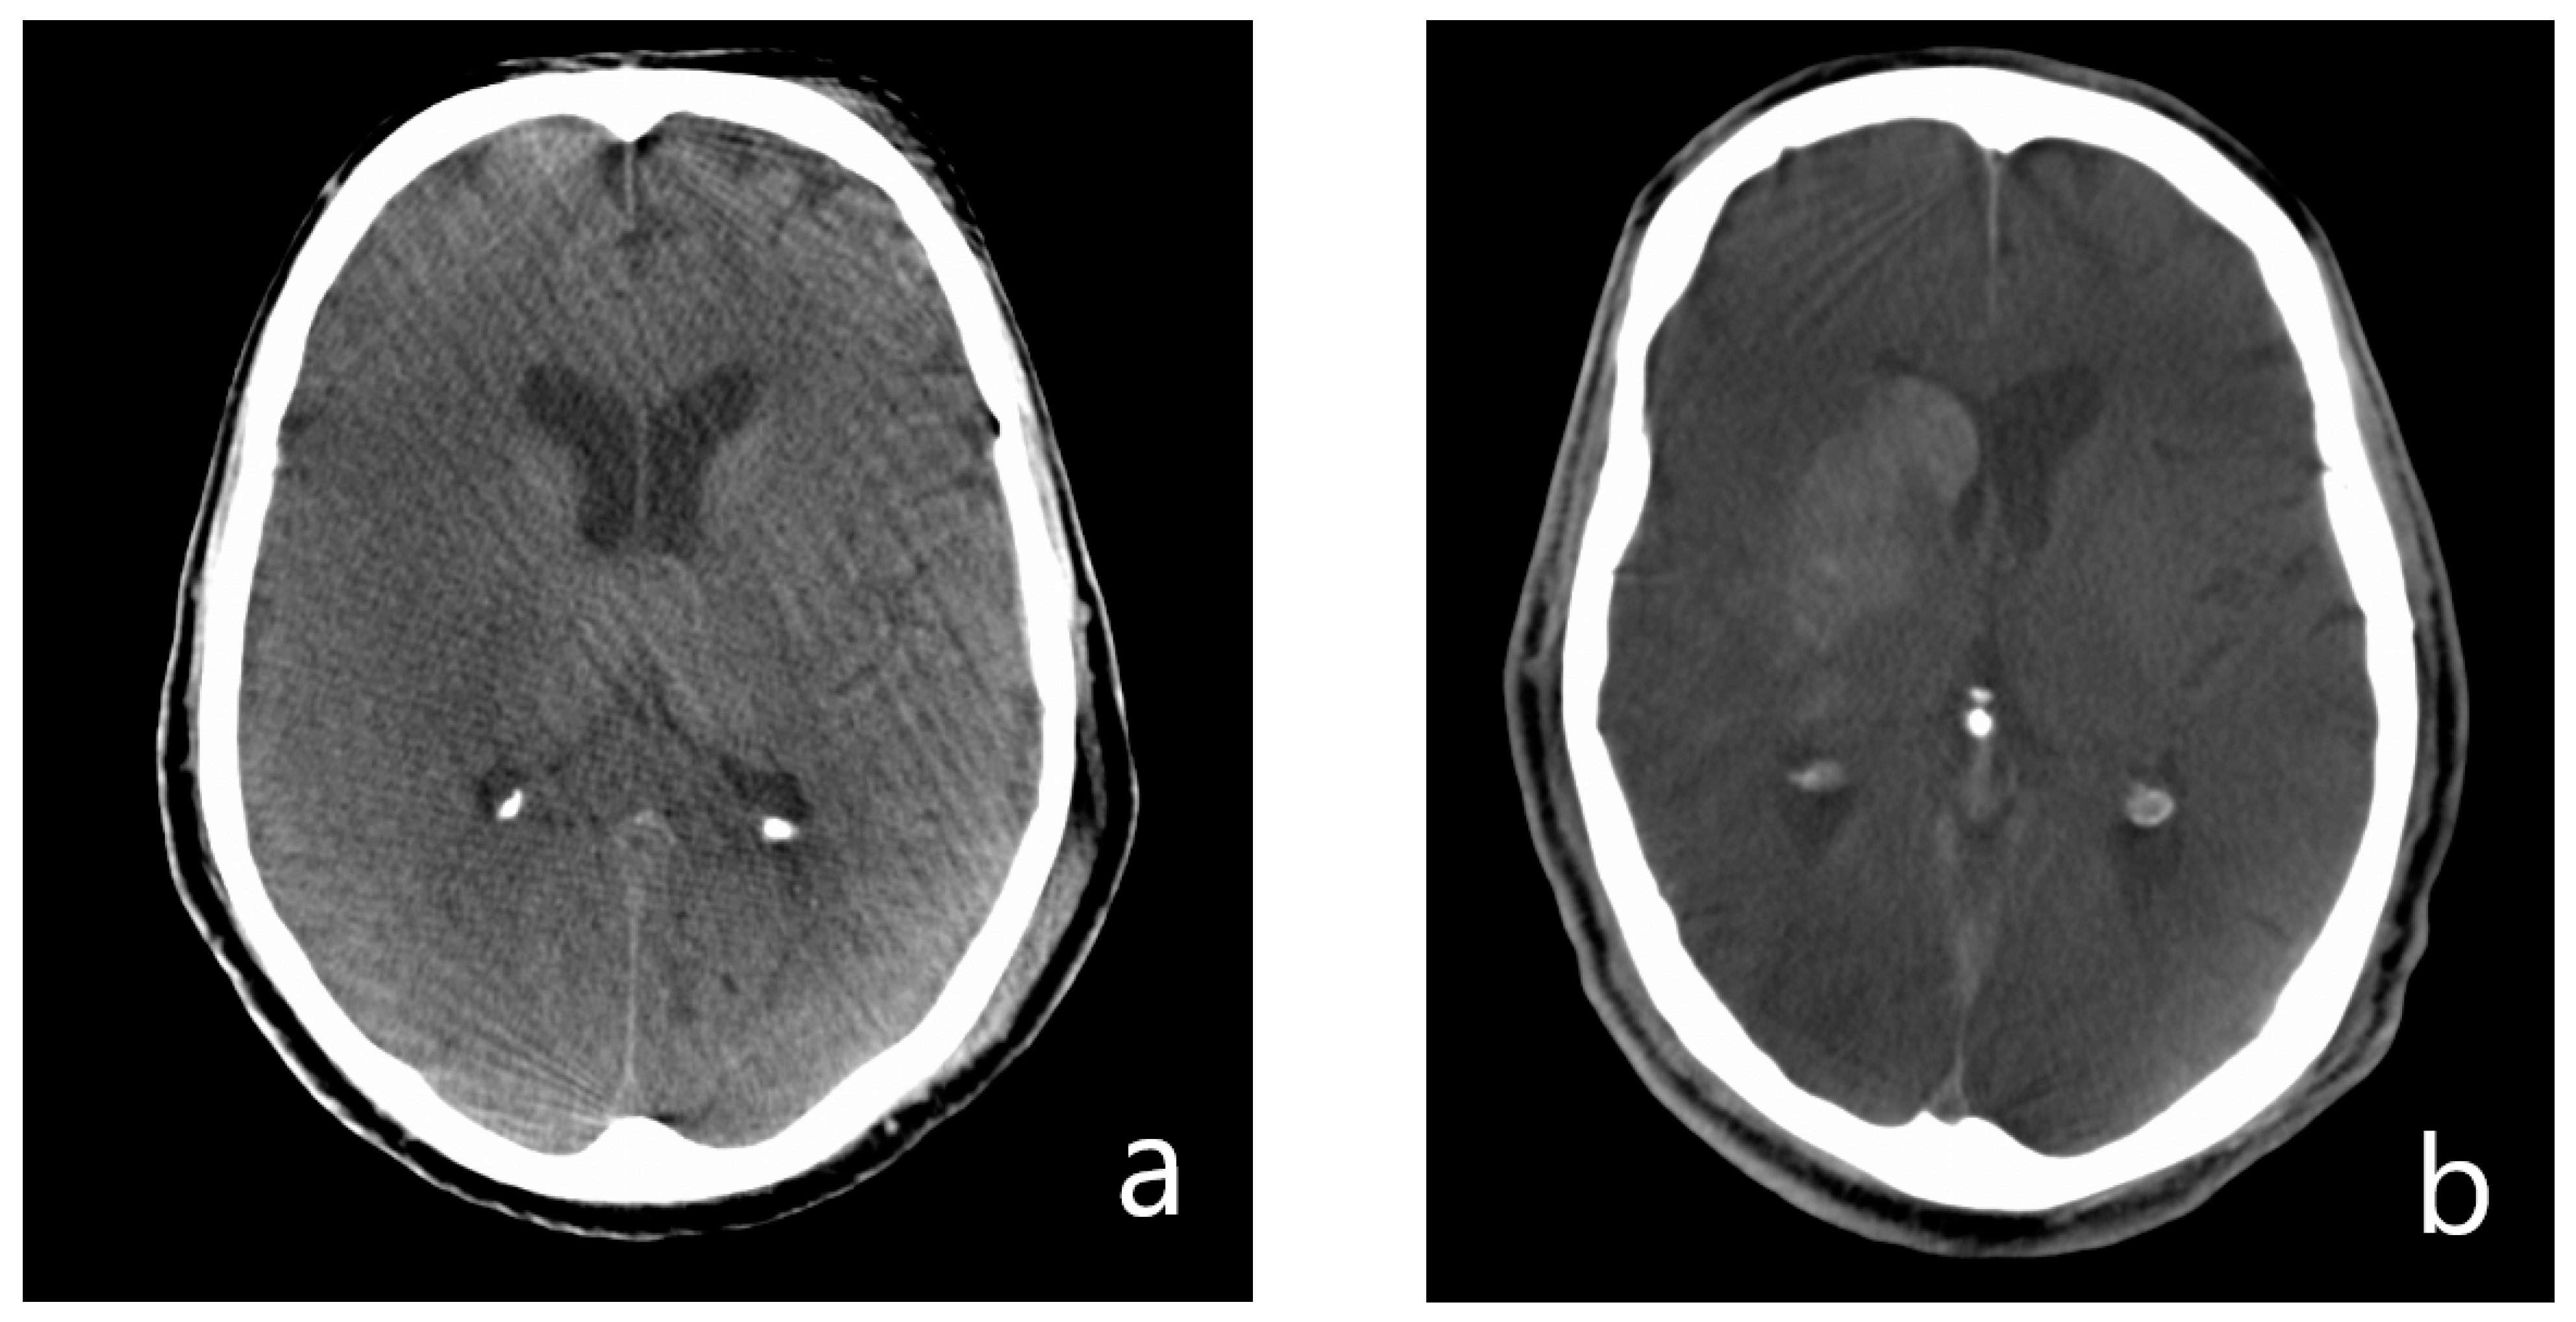

- Presence of hyperdense areas in FDCT.

- Analysis of hyperdense lesions in FDCT regarding:

- volume of the hyperdensity;

- involved brain regions (basal ganglia vs. white matter vs. cortical);

- categorising by appliance of ASPECTS.